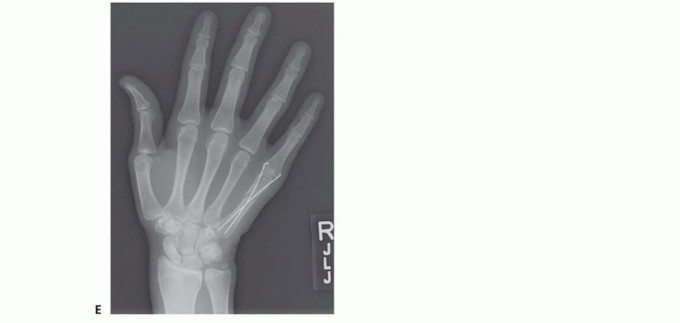

Standard radiographic imaging forms the cornerstone of diagnostic evaluation, requiring, at minimum, a dedicated posteroanterior (PA), a true lateral, and a pronated oblique view of the injured hand. The PA view is excellent for assessing coronal plane angulation and transverse displacement, though it notoriously underestimates sagittal plane deformity. The true lateral view is critical for quantifying apex-dorsal angulation, though overlapping metacarpal shadows can complicate interpretation. The pronated oblique view often provides the clearest visualization of the fracture profile and the degree of comminution.

Clinical & Radiographic Imaging Archive